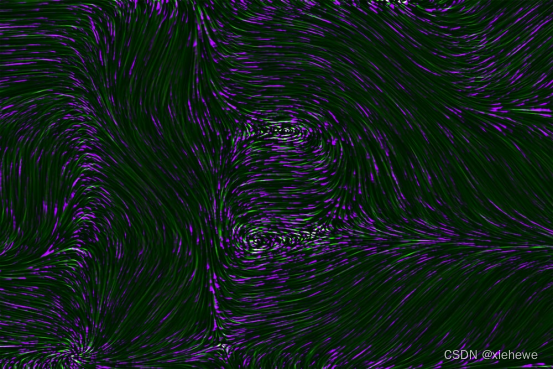

2.3医学图像分析

强化学习可以应用于医学图像分析,提高图像诊断的准确性。例如,在医学影像诊断中,强化学习可以通过学习大量的医学图像数据和对应的诊断结果,自动提取特征并辅助医生进行图像诊断,从而减少漏诊和误诊的风险。